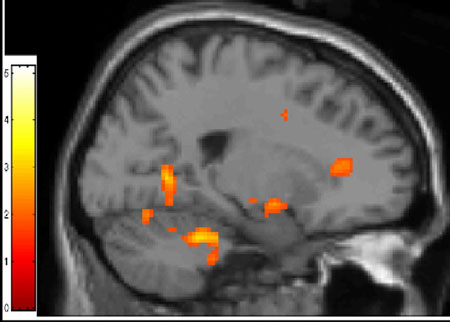

To find out, the researchers first used functional magnetic resonance imaging (fMRI), to compare responses of 12 adult BPD patients with those of 12 healthy controls to pictures of faces with fearful, angry and neutral expressions. In response to fearful faces, the amygdala, the fear hub, showed exaggerated activity in the BPD patients, while the ACC was relatively underactive. Since ACC activity would normally increase to dampen an overactive amygdala, this suggested weak regulation of emotion in the circuit.

An area (anterior cigulate cortex; orange at right) that regulates the brain's fear hub underactivated in patients with borderline personality when they viewed faces with fearful expressions. fMRI scan data reflects differences in activation between patients and controls.